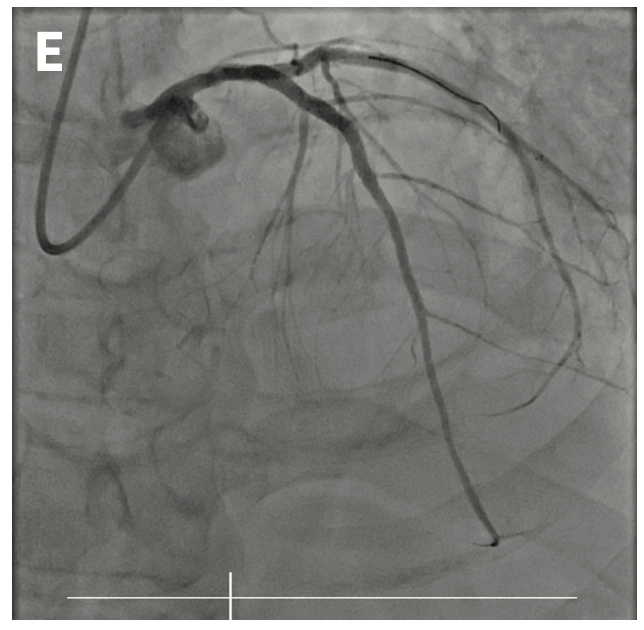

After connecting the guide catheter to the arm of the vascular robotic system (CorPath GRX from Siemens Healthineers), the targeted lesion was crossed by rotating the guidewire automatically upon retraction of the joystick. Intravascular ultrasound-guided PCI was performed to the LAD and LCx at the stent overlap (Figure 1D) using real-time stent positioning verification software (ClearStent Live from Siemens Healthineers). Staged PCI to the totally occluded RCA was performed robotically by again using built-in software automation to rotate the guidewire following joystick retraction to redirect the guidewire tip (Figure 1E), as well as to oscillate the guidewire as it advanced through the vessel (Figure 1F). During the entire case, the primary operator of the vascular robotic system remained in the control room while the secondary operator remained at the patient’s bedside.